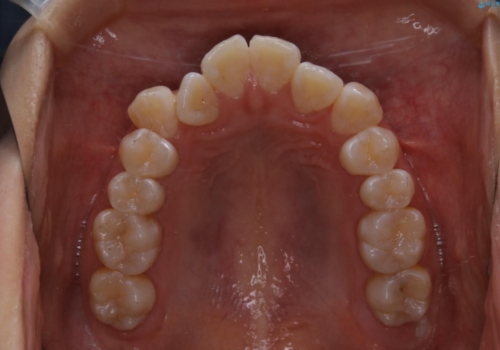

前歯のがたつきとオープンバイト:インビザラインでまとめて治す

- 噛み合わせと、前歯のがたつきが気になるとご相談にいらした方です。インビザラインFULLで綺麗な歯並びと噛み合わせを作ることが出来ました。

オープンバイトの方への治療は、通常抜歯を行いワイヤーによる矯正治療を行うことが多いですが、今回はインビザラインの特性を生かし、非抜歯にて綺麗な歯並びを作ることが出来ました。

舌癖がある方は、歯を内側から押し出す力が日常的に働くため、矯正治療後も歯と歯の隙間が開いてしまうなどの後戻りのリスクが高いことが知られています。舌の正しいポジショニングやお口周りの筋肉のトレーニングを行うことで後戻りのリスクを減らすことが可能です。